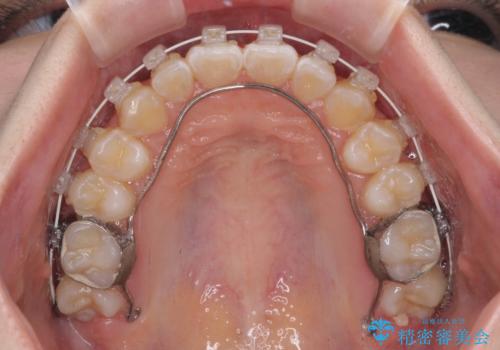

- 審美装置

左右ともに上顎第二大臼歯が外側に転位しており、大変磨きにくくなっているため、補助装置により内側に引き込むことで改善することとしました。

外側を向いていた奥歯は比較的早い時期に歯列に収まり、咬み合わせも磨きやすさも改善することができました。